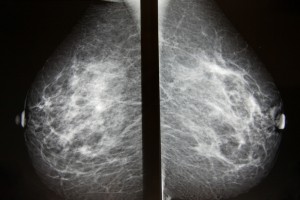

Bröstcancerscreening kan bli bättre och mindre smärtsam

De bröstcancerundersökningar som erbjuds kvinnor kan i många fall vara onödigt smärtsamma. Ny forskning från Lunds universitet och Skånes universitetssjukhus visar att hårt tryck mot bröstet i samband med mammografiscreening inte automatiskt leder till bättre…